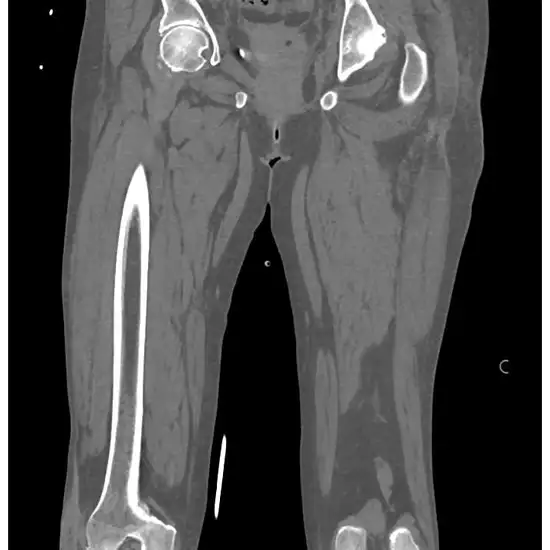

NCCT Right Thigh is a plain scan to visualize the bones of the right thigh along with the surrounding soft tissues like the cartilage, tendons, ligaments, muscles, and blood vessels.

NCCT (non-contrast computed tomography) screening of the Right Thigh is a non-invasive radiology test used to evaluate the condition of the Right Thigh and surrounding tissue. NCCT Right Thigh is done to look for the conditions of the Right Thigh and the surrounding area.